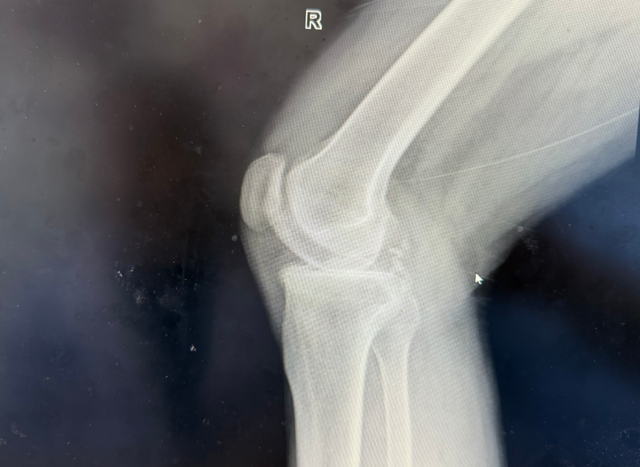

张大叔的右膝MR显示:半月板撕裂、软骨III级损伤、骨髓水肿……“就像轮胎磨穿了还漏气,膝盖里没有一块好地方。”尹绍猛解释道。传统方案需切除更多骨质,而生物型置换通过精准截骨,最大限度保留健康骨量。

术前影像